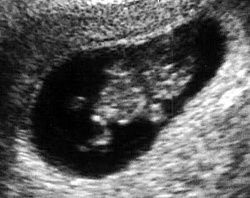

الأسبوع العاشر:

يبدأ في هذا الأسبوع حدوث تغيرات نفسية ومزاجية للأم فتكون متقلبة المزاج بشكل كبير مع بداية هذه الفترة ولكنها تكون فترة قصيرة ويستمر الحمل بعد ذلك بشكل طبيعي وتحدث هذه التغيرات بسبب اضطراب الهرمونات الأنثوية في الجسم.

يصبح الجنين في نهاية هذا الأسبوع حوالي 3.75 سم وحوالي 9.3 جرام. بالنسبة للجفون فهي ملتحمة مع العين وتبقي هكذا حتى الأسبوع السابع والعشرين. يستمر المعصم في النمو هذا الأسبوع ويتكون الكاحل وتبدأ أصابع اليد والقدم في الظهور ويزداد طول الأذرع.

ينتهي التكوين الداخلي للأذن في نهاية هذا الأسبوع. بالرغم من عدم إمكانية تحديد نوع الجنين (ذكر أم أنثي) في هذا الوقت عن طريق الموجات فوق الصوتية ولكن تبدأ الأعضاء التناسلية في التكوين هذا الأسبوع.

وتكتمل المشيمة الآن وتبدأ في القيام بوظائفها كاملة وأهمها إفراز الهرمون. بالنسبة للسيدات فوق سن 35 أو إذا كان هناك تاريخ مرضي للعائلة له علاقة بالأمراض الوراثية، فيجب القيام بعمل فحوصات طبية ما بين الأسبوع الأول والعاشر والتي تحدد إذا كان هناك أي نمو غير طبيعي للجنين